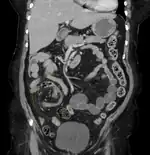

| Coronal CT of the abdomen, demonstrating a volvulus as indicated by twisting of the bowel stock | |

Coronal view of sigmoid volvulus with "whirlpool sign"